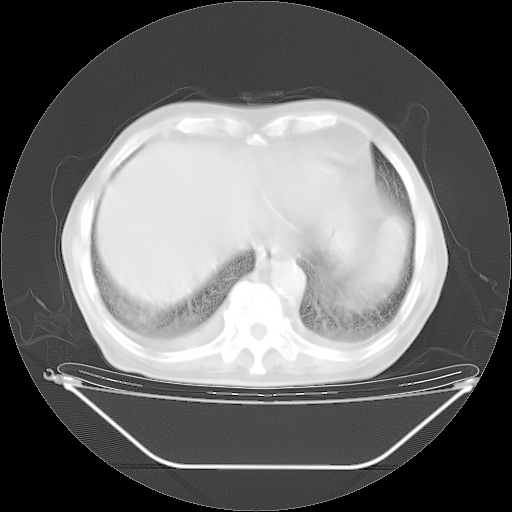

5月9日肺部CT(在4月27日齐鲁医院肺部CT描述部分肺组织磨玻璃样改变,12天后肺组织广泛磨玻璃样改变)

2009年5月9日肺部CT

大致读了系列胸部CT:纵隔窗无明显异常,肺窗:从4、27至今:主要是双肺中下野外带可见毛玻璃样改变,目前处于急性肺泡炎阶段,至于原因考虑1、结替组织或胶原血管性疾病所致?2、恶性疾病如恶组在肺部所致的表现或细支气管肺泡癌?3、药物或其它原因如肺蛋白沉着症所致肺泡炎目前不太可能?总之,明天就去请我院的呼吸科、感染科、血液科和临免专家会诊哈。